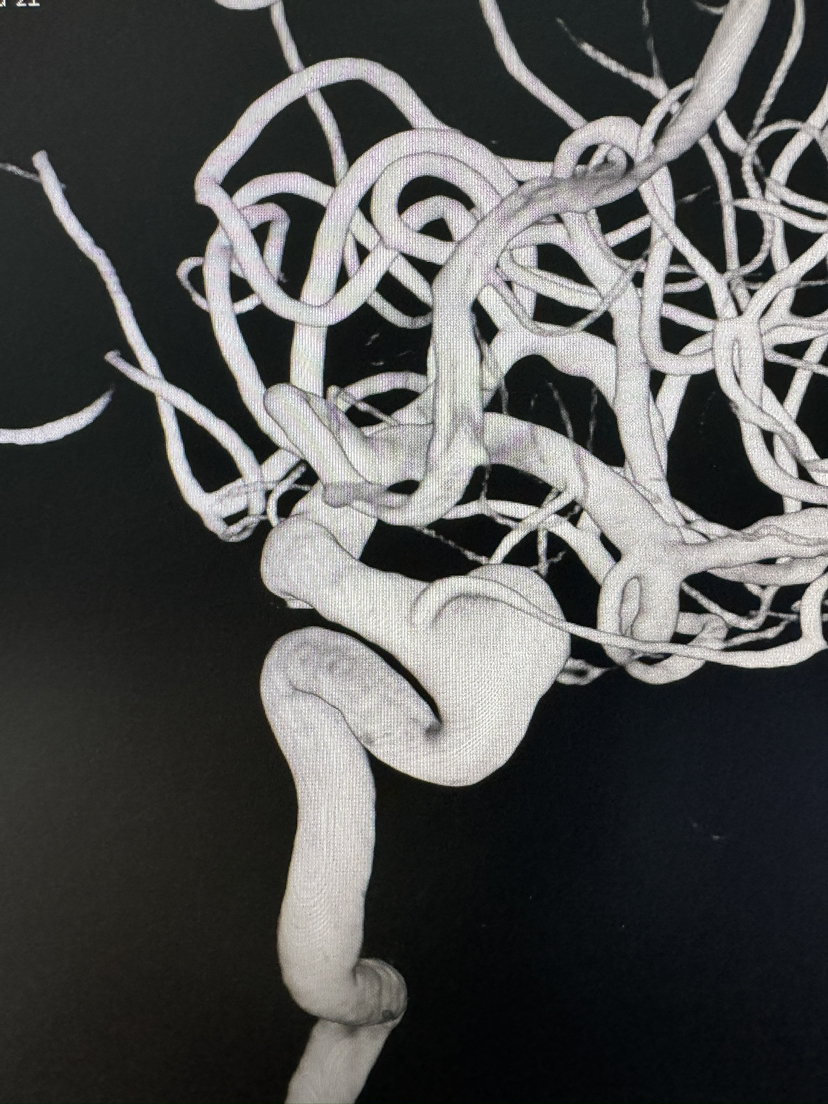

Lattice 支架治疗眼动脉动脉瘤,Scepter c 球囊后扩辅助海绵窦段支架打开